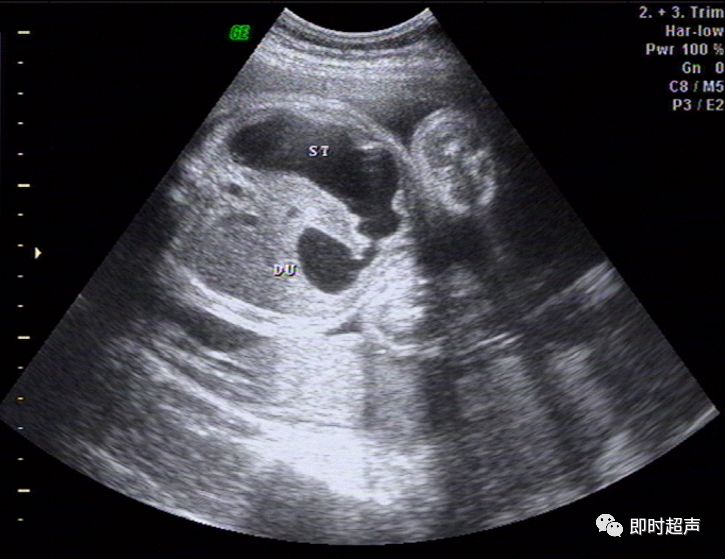

超详细图文胎儿中晚孕超声常用切面及胎儿常见异常畸形